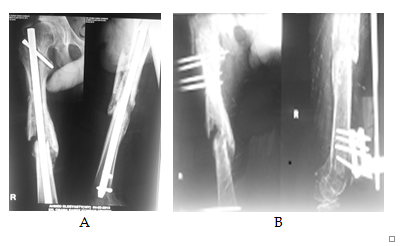

Excluded from this study any patient who already developed pathological fracture. Different types of fixation either surface plating (dynamic hip screws) (Figure 3 & 4) medullary (Gamma nails) (Figure 5) or external fixation in cases unsuitable for surgery (Figure 6) were used according to the type and the site of the deformity. In tibial cases, we used the tourniquet without blood evacuation in the limb.

Figure 4 Preoperative X-rays of a lesion at the proximal end and neck of the femur (loser zone), the lesion is more than half of the diameter with an impending fracture at the neck of the femurs (A and B). C and D post operative prophylactic fractures fixation by dynamic condylar plate. E shows 2 years follow up.